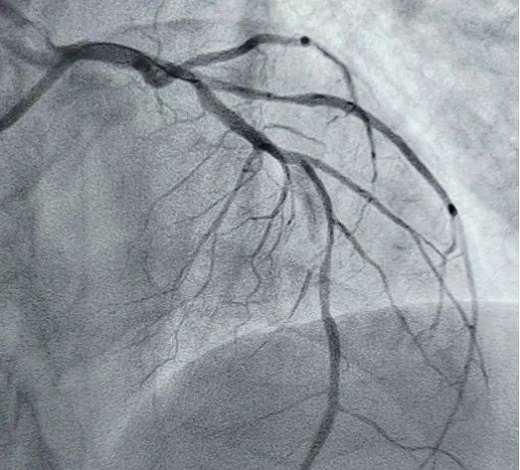

立即啟動綠色通道,急診冠脈造影,結(jié)果顯示前降支近段閉塞,血栓負(fù)荷較重,先后給予血栓抽吸及球囊擴張,血流恢復(fù)正常。李桂武主任和劉興剛主任發(fā)現(xiàn)患者近段狹窄達70%,且中遠段嚴(yán)重狹窄伴鈣化,此時不適合同期植入支架,如植入支架可能會引發(fā)血管破裂危及生命。當(dāng)務(wù)之急是快速評估出患者是否可以下手術(shù)臺,選擇擇期進行處理,但僅根據(jù)造影結(jié)果又很難做出判斷,李桂武主任和劉興剛主任快速討論研究最后一致決定,給予患者行冠脈OCT檢查,明確病變性質(zhì)。

經(jīng)OCT檢查結(jié)果顯示:前降支中段鈣化,內(nèi)膜光滑,最小管腔面積僅為1.19 mm2。近段斑塊破裂,可見血栓影,最小面積為2.63mm2。可選擇先進行抗栓治療,擇期處理冠脈病變。這讓張先生懸著的一顆心終于放下來。